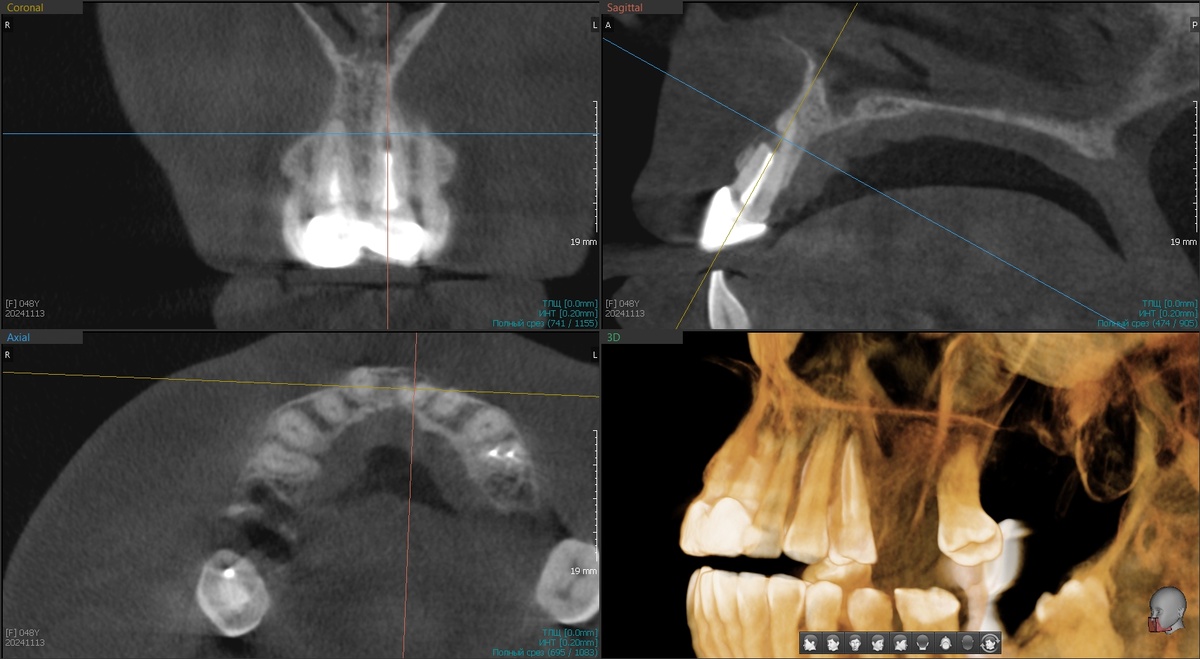

Сделали снимок КЛКТ и обнаружили проблему во фронтальном отделе верхней челюсти:

Зуб 2.1, первый левый резец, имеет дефект корня где-то на глубине, ближе к верхушке. От чего такое могло произойти? Причину резорбции мы не можем никогда на 100% точно установить. Но тут есть мыслишки - раз дефект на уровне вкладки, то, скорее всего, причина в ней.

Мы пациентку предупреждали сразу - может ничего не получиться. Когда корень толще основания кости, в которой он находится, гарантировать успех имплантации невозможно.

В тонкой части всего 4 мм

То место, что обозначено "толсто" - схлопнется до уровня "тонко" после удаления зуба. Если бы "толсто" было повсеместно, то мы бы расслабились и подвоха не ожидали.